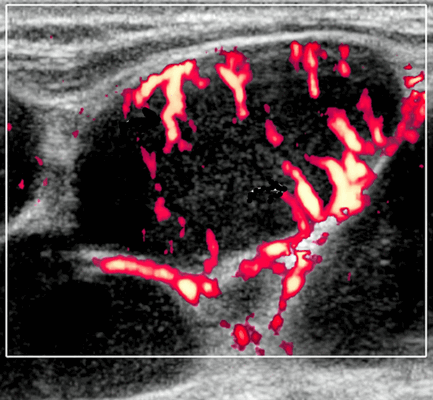

Цветной допплер. Узловая НХЛ. Выраженная центральная или внутриузловая гиперваскуляризация. Паренхима при неходжкинской лимфоме более диффузная железистая гиперваскуляризация. Васкуляризация от умеренной до выраженной в плохо очерченных образованиях.

- Цветной допплер: смешанная васкуляризация с выраженным сосудистым рисунком и наличием периферической васкуляризации. Периферическая сосудистая сеть редко встречается в узлах НХЛ

Цветовой допплер: смешанная сосудистая сеть с выраженными внутриузловыми сосудами и наличием периферической сосудистой системы. Одна только периферическая сосудистая сеть редко встречается в узлах НХЛ. Спектральный допплер: переменное интранодальное внутрисосудистое сопротивление, которое носит неспецифический характер.